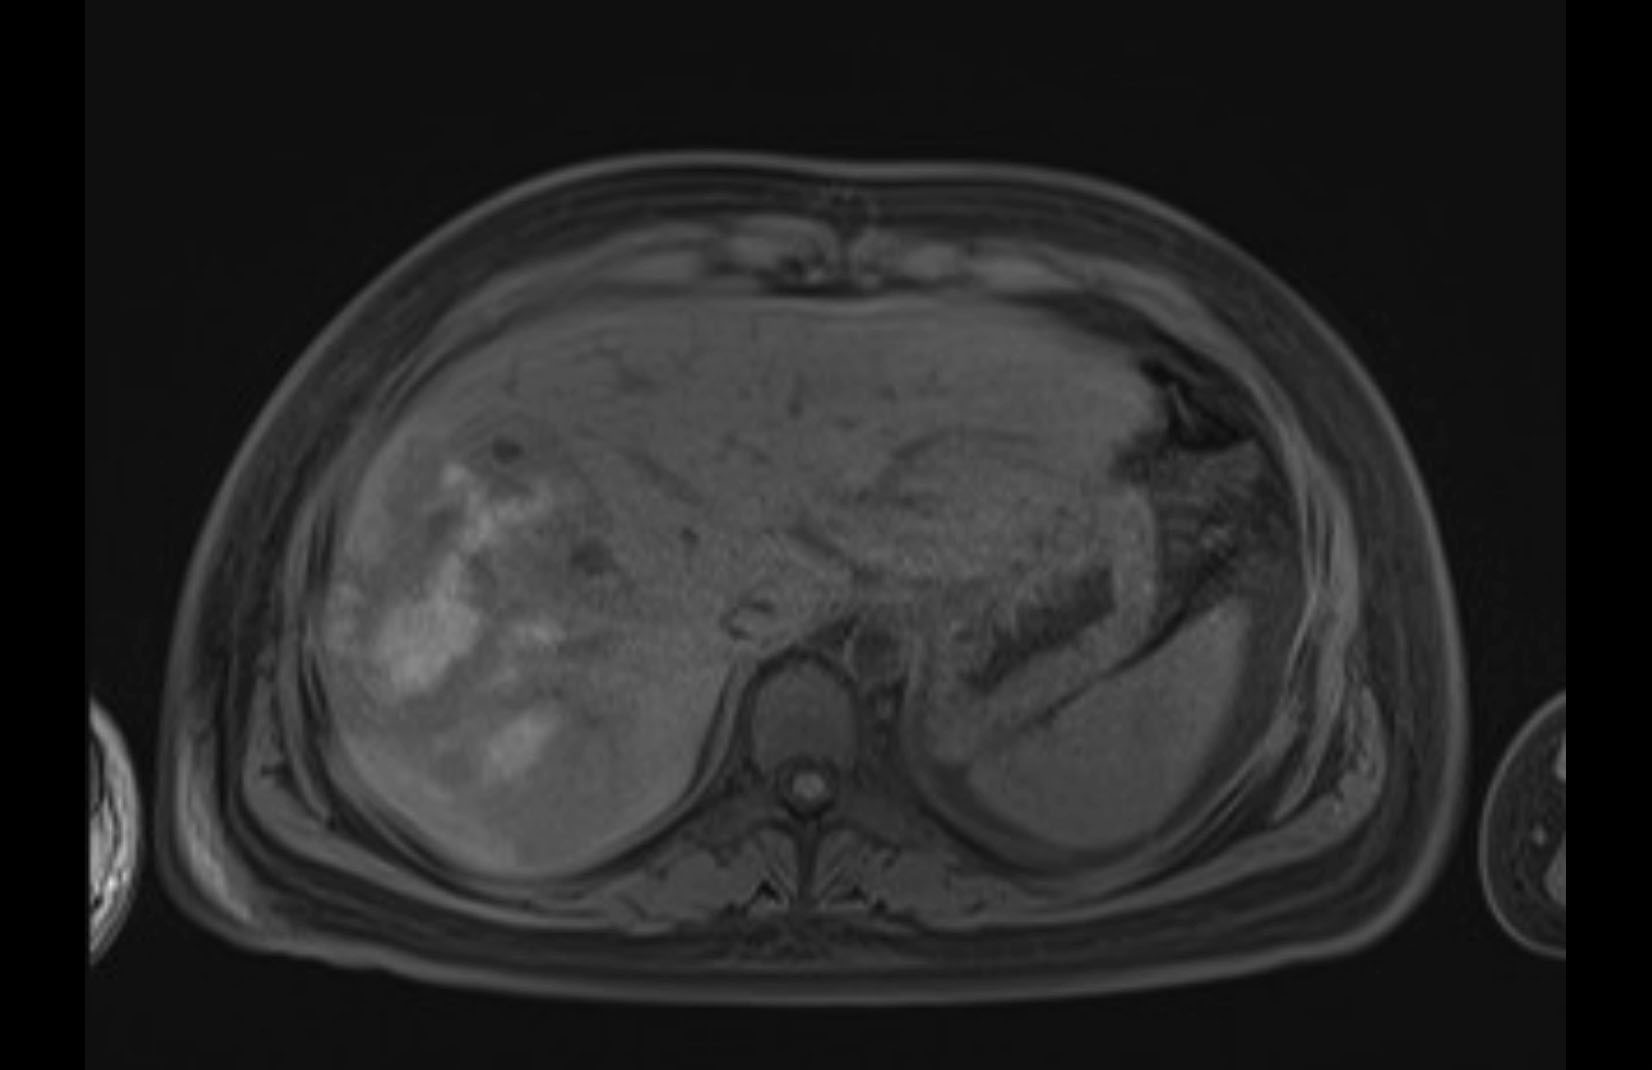

MRI T1

Imaging analysis

Based on initial findings, which issue(s) would you be most concerned about?